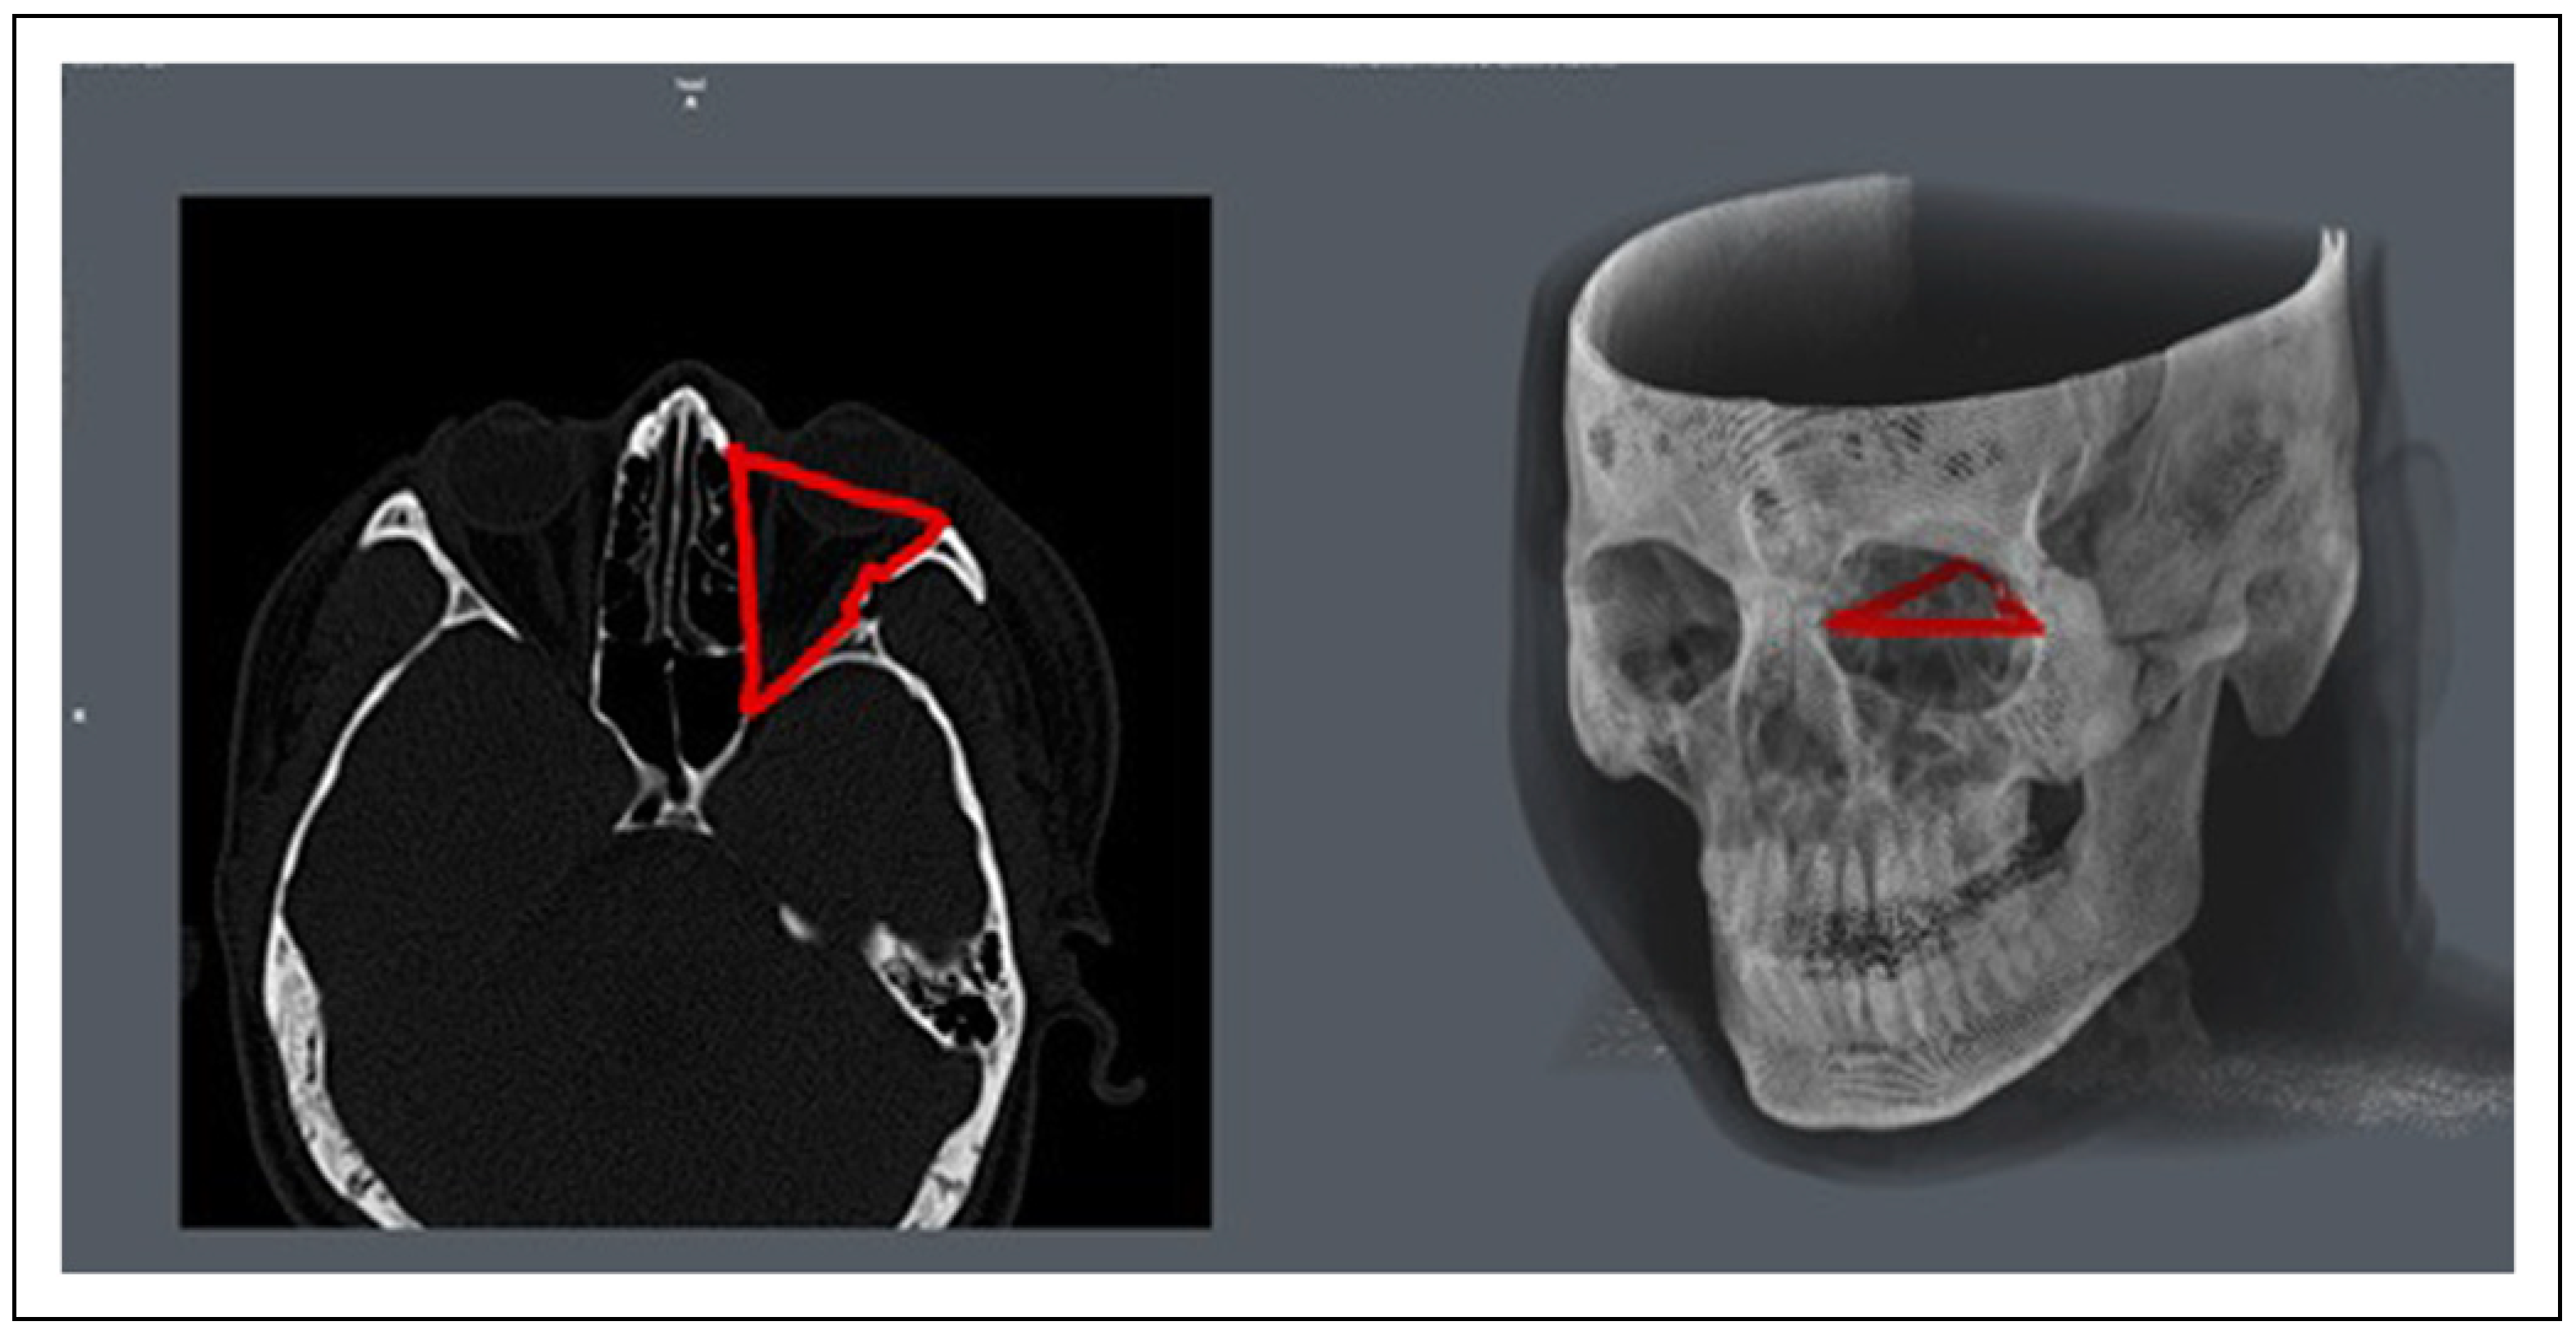

- The interface screen displayed the cross-section of each slice in a 2D format on the left and the 3D rendering of the patient on the right. (Figure 1).

- In each axial section image, the margins of the orbit were manually selected by using the “Draw” option of the Region of Interest (ROI) tool. (Figure 2) For volume calculation of each orbit, the marking on every axial section was added to the same ROI. The anterior boundary was determined by a line joining the medial and lateral orbital rims. The posterior boundary was defined by the initiation of the optic foramen, inferior and superior orbital fissure [4].